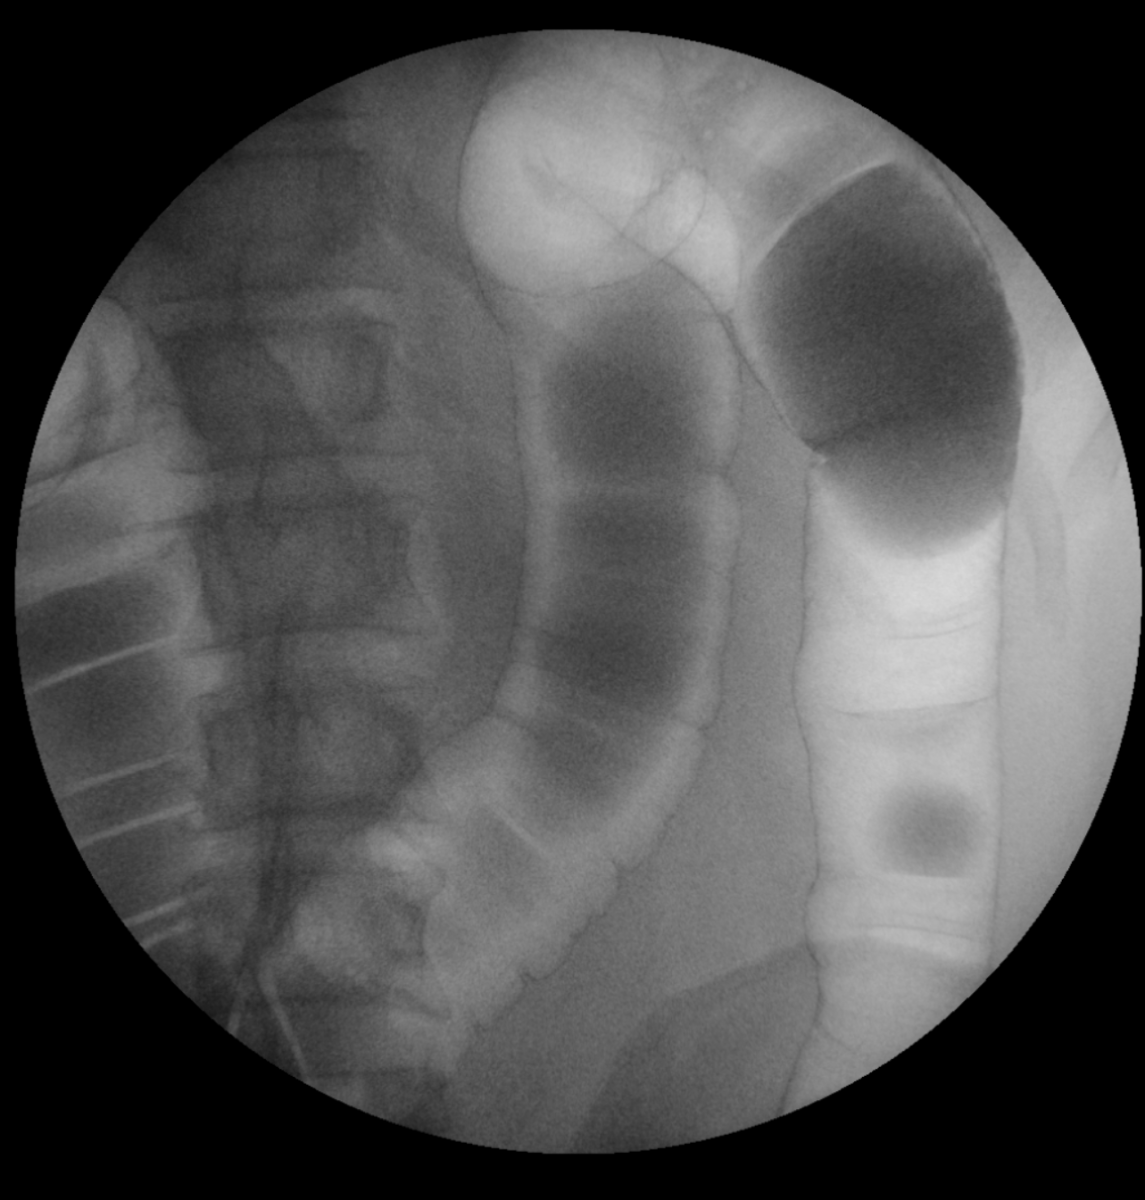

Jedná se o radiologickou vyšetřovací metodu, která pomocí rentgenového záření umožňuje zobrazení lidského těla v reálném čase. Využívá se především k zobrazení trávící trubice (jícnu, žaludku, dvanácterníku, tenkého a tlustého střeva), zobrazení žlučového stromu (ERCP), zobrazení ostatních dutých orgánů – na našem pracovišti zejména močového měchýře a vývodných cest močových, dále některých patologií (píštěle…) apod. Orgány jsou zobrazovány pomocí kontrastní látky, která zabraňuje průchodu rentgenového záření.

Jak je napsáno výše, nejčastější využití skiaskopie je při vyšetření trávicí trubice. Pro její zobrazení je nutné podání kontrastní látky. Nejčastější kontrastní látkou je baryová suspenze, která má různou hustotu, dle vyšetřované oblasti, má bílou barvu a chuť podobnou křídě, ve většině případů pro komfort pacienta doplněnou různými, převážně ovocnými příchutěmi. Při vyšetření se navíc používá plyn pro dosažení tzv. dvojího kontrastu – přímo aplikovaný při vyšetření tlustého střeva.